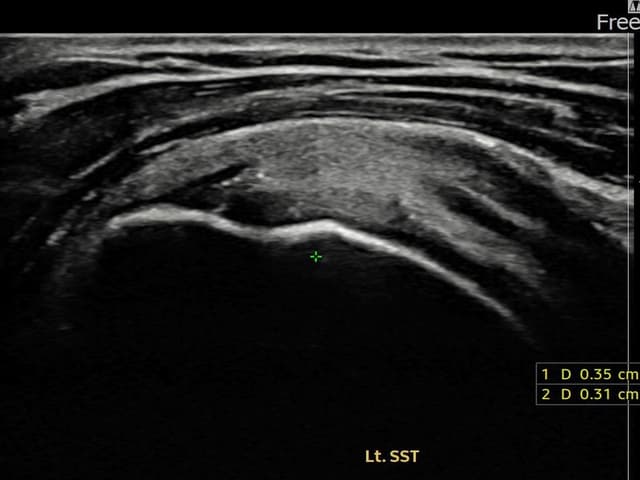

左侧 冈上肌腱 关节面侧部分撕裂

3.5mm × 3.1mm (부분파열)

左侧 冈上肌腱 附着部部分撕裂

5mm × 3mm (肌腱厚度约25%缺损)